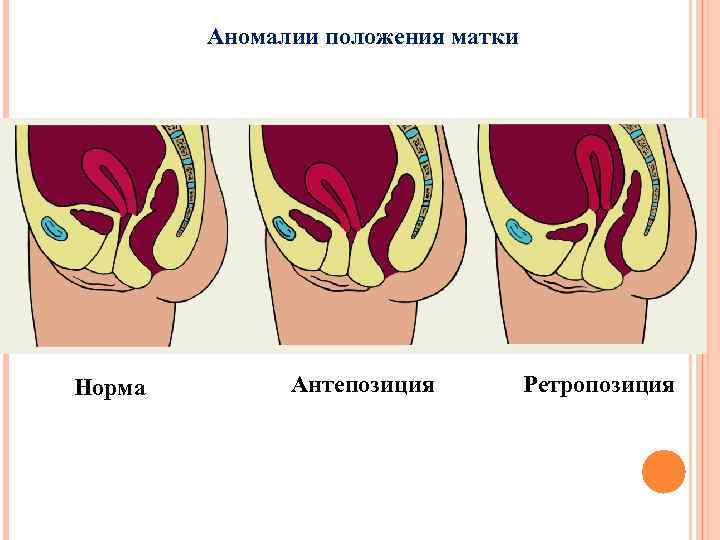

Аномалии положения матки Норма Антепозиция Ретропозиция

Аномалии положения матки Норма Антепозиция Ретропозиция